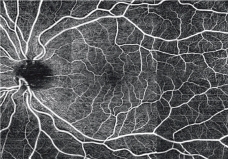

HD8スキャン

HD8スキャンは、高コントラスト・低ノイズの画像が取得できます。

スキャン数は、HD2スキャン、HD4スキャン、HD8スキャンが選択できます。

同範囲で撮影をした場合、HD8スキャンの方がより鮮明に画像を取得することができます。

3×3mm HD8スキャン |

3×3mm HD4スキャン |